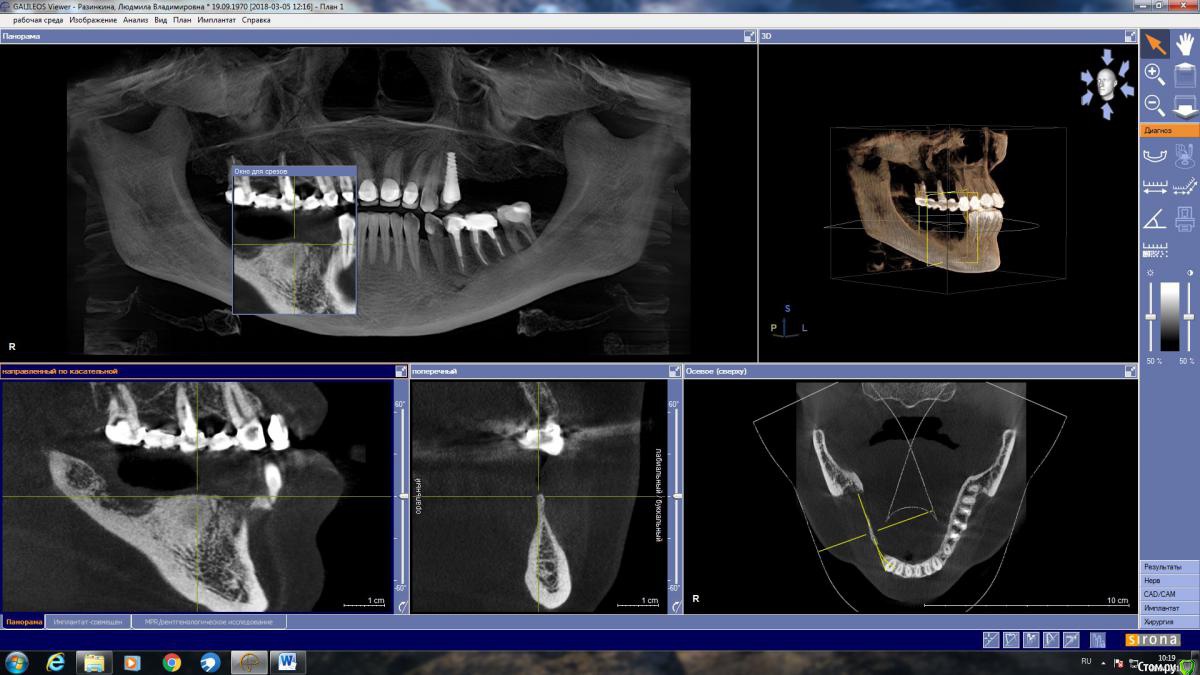

LjudmilaRaz Опубликовано 27 апреля, 2018 Поделиться Опубликовано 27 апреля, 2018 Здравствуйте! Напишите, пожалуйста, своё мнение. В первую очередь планирую имплантацию снизу справа!Обращалась на консультацию к трем врачам. Первый имплантолог предложил нарастить кость и установить четыре импланта. Врач работает только с имплантами одной фирмы (немецкие). Смутило, что полгода назад вариант был совершенно другой и еще то, что очень дорого.Второй предлагает нарастить кость и установить имплант Астра на месте удаленной в декабре четверки со смещением ближе к месту пятерки, и имплант Анкилоз на месте семерки со смещением к шестерке. То есть, накрыв мостом, получится не четыре, а три зуба.Такой же вариант, но с южно-корейскими имплантами (работаю только с ними), предложил третий имплантолог. Это относится к случаю, когда если двое говорят разное, то стоит послушать третьего ? Ссылка на комментарий

LjudmilaRaz Опубликовано 10 мая, 2018 Автор Поделиться Опубликовано 10 мая, 2018 Здравствуйте!С врачом определилась, опытный ЧЛХ стоматолог-имплантолог, еще раз сходила на консультацию. Он считает, что в моем случае более щадяще будет использование костной пластины животного происхождения, которая, становясь после определенных манипуляций пластичной, обогнет с обеих сторон в районе 4 и 5 снизу справа, где в дальнейшем планируется установка двух имплантов (плюс еще один в районе 7-ки - в итоге 3 штуки). По его мнению, ранее им планируемое расщепление в моём случае может стать по факту невозможным, из-за анатомически неблагоприятной ситуации - мало кости. Есть место (практически 2 мм) где при рассечении кость может "съесться" инструментом.Только в моей голове всё сложилось, и тут новый виток. Что думаете про такой способ костной пластики для моего случая. Ссылка на комментарий